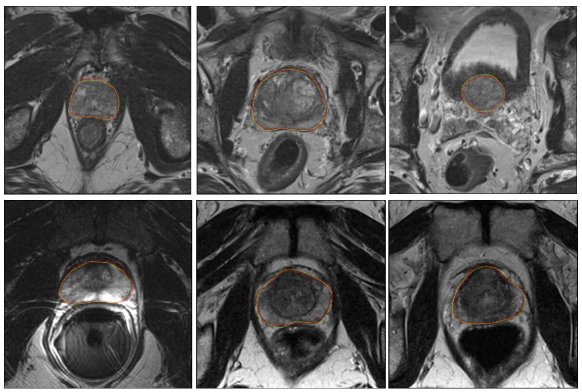

Refer to caption

Figure 4: Segmentation results of the prostate from MR images. The yellow and red contours indicate the ground truth and our segmentation results, respectively. Note that these results are directly obtained from challenge website.

Several sample results of our proposed method are shown in Fig. 4. It can be seen that our model can accurately segment the prostate and obtain smooth and continuous prostate boundaries. Quantitative evaluation was also performed. The evaluation metrics used in PROMISE12 challenge include Dice Similarity Coefficient (DSC), percentage of the absolute difference between the volumes (aRVD), average over the shortest distance between the boundary points of the volumes (ABD) and Hausdorff Distance (HD). All the evaluation metrics are calculated in 3D. In addition to evaluating these metrics over the entire prostate segmentation, the challenge organizers also calculated the boundary measures specifically for the apex and base parts of the prostate, because those parts are difficult to segment but in the same time very important for many clinical applications. The apex and base the prostate are determined by dividing the prostate into three approximately equal sized parts along the axial direction (the first 1/3 as apex and the last 1/3 as base). Then an overall score will be computed by taking all the criteria into consideration rank the algorithms.

The results of our proposed method and the competitors are shown in Table 2. Only the top 10 teams are listed. Note that all the results reported in this section were obtained directly from the challenge website. As it can be seen from the table, our overall performance was the best and therefore ranked the first place among all the teams (by May 22, 2018)555https://promise12.grand-challenge.org/evaluation/results/ with the score of 89.18. From Table 2, it can be seen that our proposed model achieved the best performance in several measures. The segmentation results of our model were the best not only for whole prostate segmentation, but also in the base and apex areas, which demonstrates the effectiveness of the proposed 3D model with DRBs and AM modulated long connections.